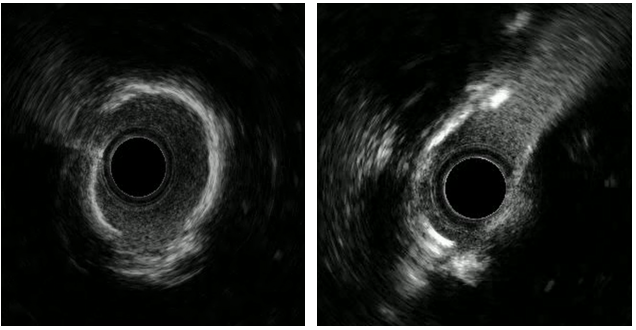

左主干-回旋支行IVUS检查;

回旋支近中段可见弥漫性狭窄伴有360°环形钙化;

回旋支开口面积2.1平方毫米;

左主干-前降支IVUS导管不能通过。

切割球囊切割后行IVUS检查提示钙化环有所断裂,回旋支开口狭窄仍严重,遂决定使用2.5mm NC球囊高压扩张。

复查造影后再次复查前降支IVUS

前降支近中段支架膨胀不全;

遂3.5mm球囊高压扩张;

结合术后IVUS,考虑该处钙化严重及钙化小结导致IVUS导管及球囊无法通过。

复查造影支架贴壁良好

回旋支支架植入后因支架及钙化原因,IVUS导管无法推送至中段以后,遂仅对回旋支开口支架IVUS检查。

回旋支开口支架后扩后行IVUS检查:支架贴壁膨胀良好。